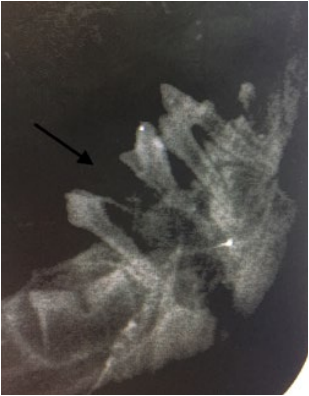

- Отсутствие постоянного преемника – состояние, при котором отсутствуют зачатки постоянных зубов (фото 3):

- гиподентия – отсутствие от одного до пяти постоянных зубов;

- олигодентия – отсутствие более пяти единиц постоянных зубов;

- адентия – полное отсутствие зубов.